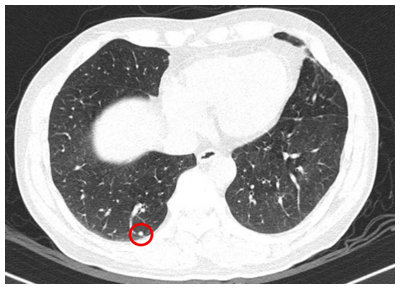

- Chụp cắt lớp vi tính ngực(06/08/2025) – sau phẫu thuật:

Hình 4: Hình ảnh chụp cắt lớp vi tính lồng ngực: Hình ảnh các nốt đặc rải rác 2 bên phổi, nốt lớn nhất kích thước 4mm (vòng tròn đỏ).